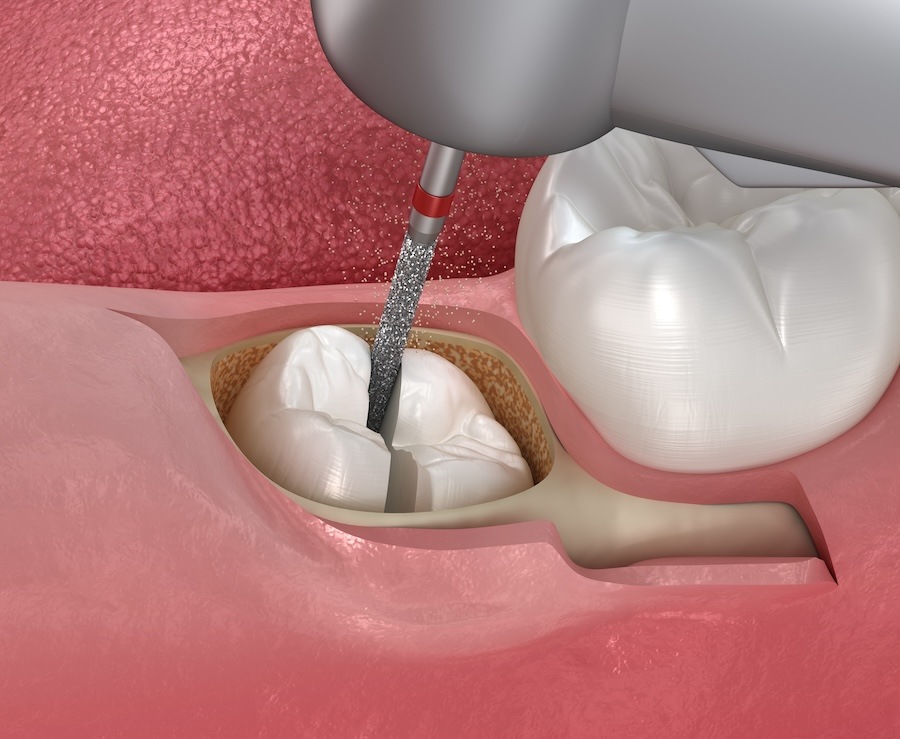

Oral Surgery